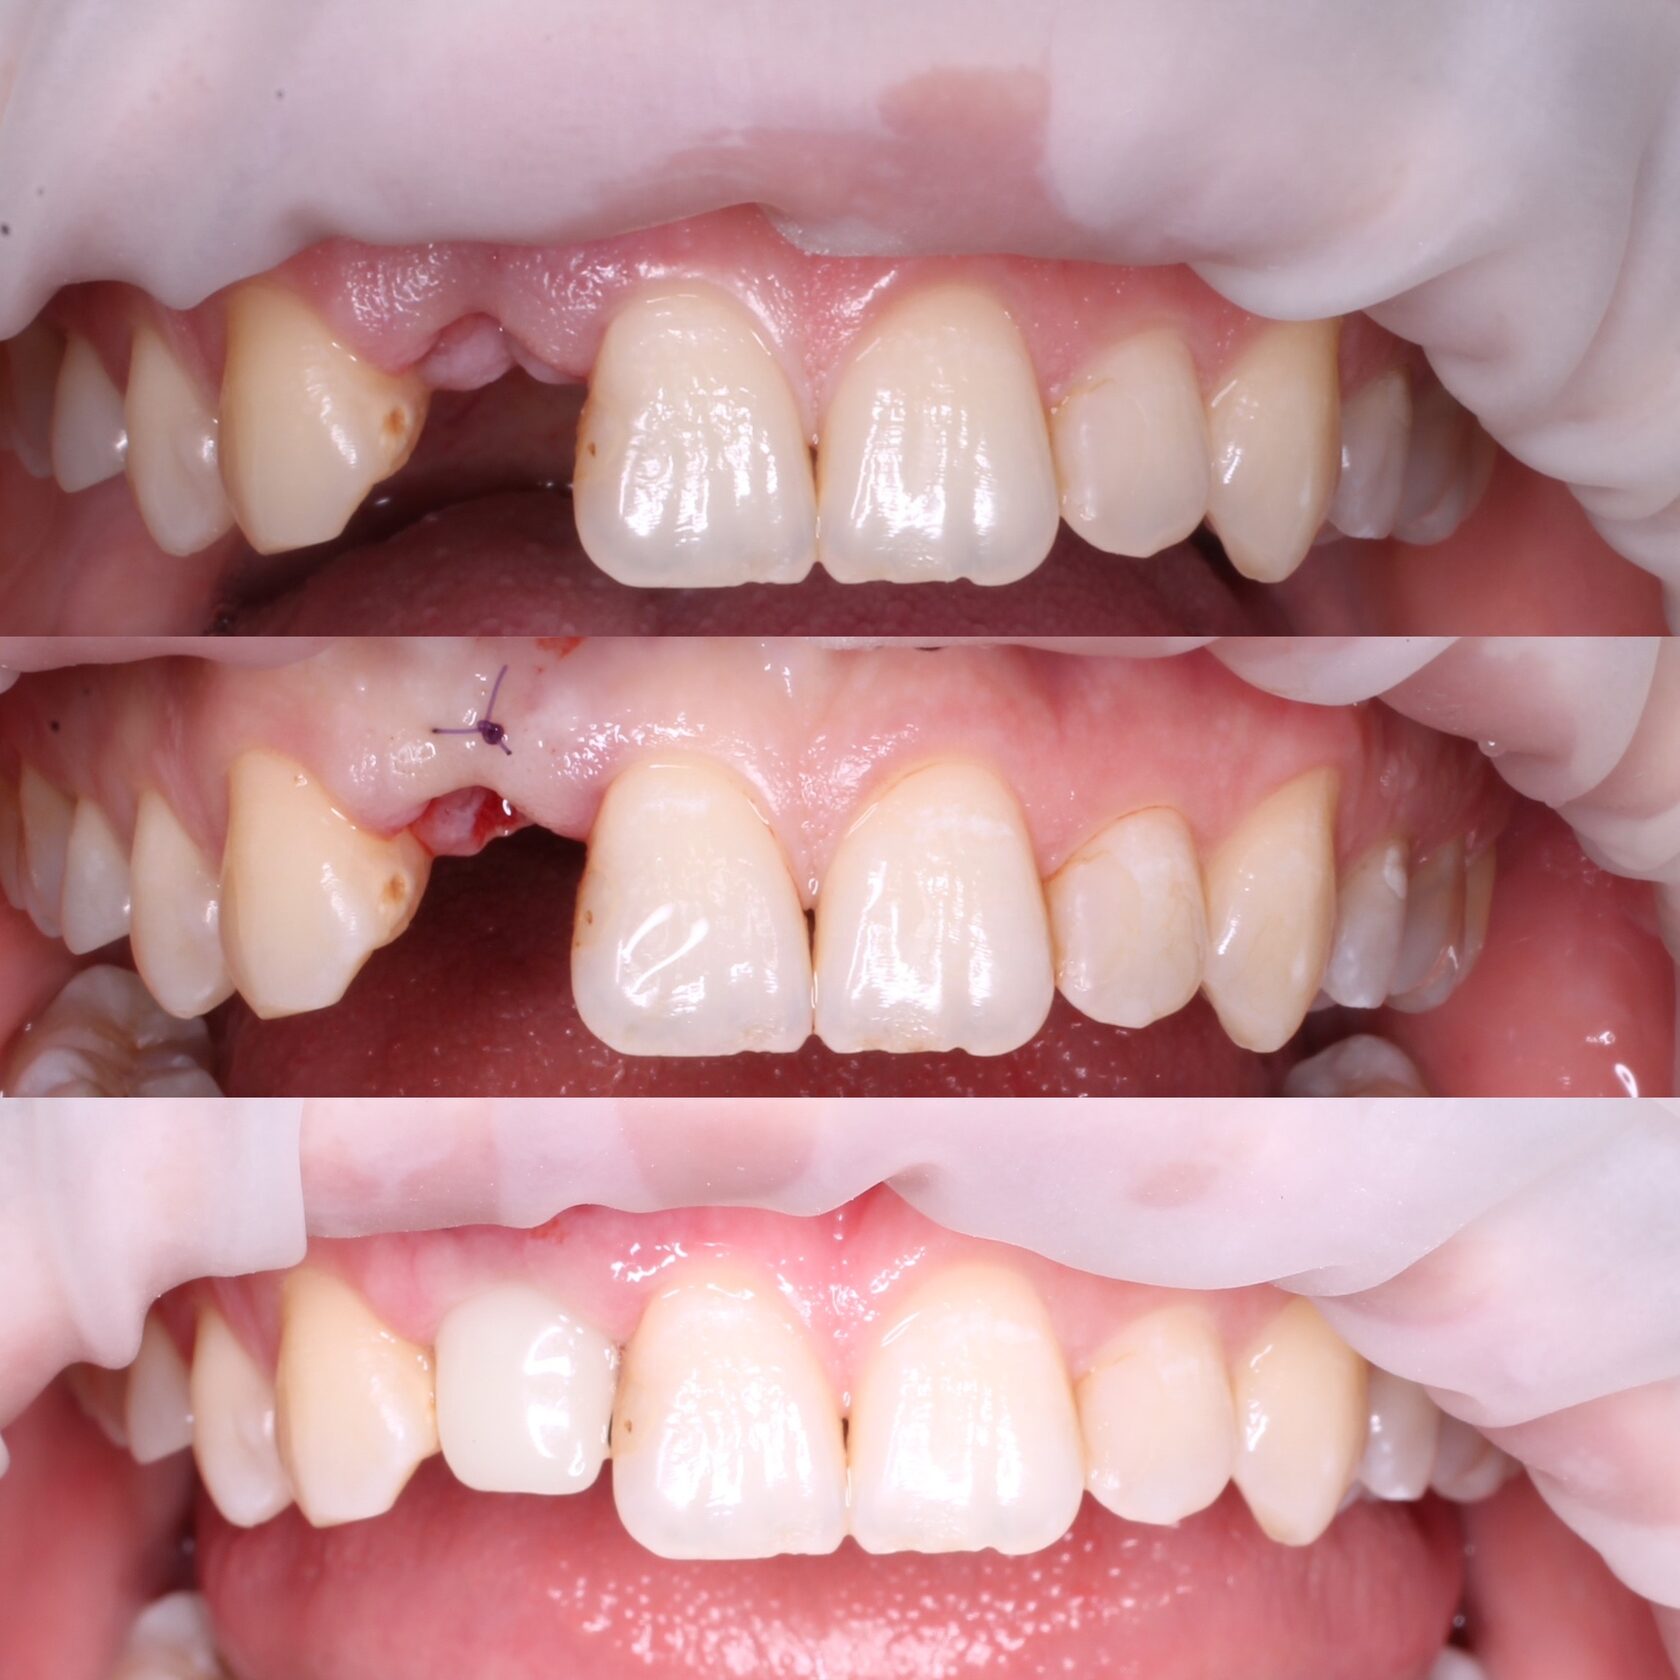

Имплантация зубов с хирургическим шаблоном